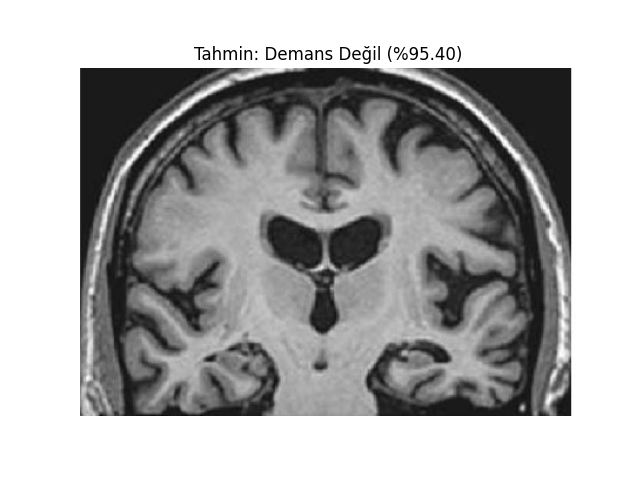

def show_image_with_prediction(image_path, prediction, confidence, class_names):

image = Image.open(image_path)

plt.imshow(image)

plt.title(f"Tahmin: {class_names[prediction]} (%{confidence * 100:.2f})")

plt.axis('off')

plt.show()

test_image_path = 'MRI/veya/fMRI/görüntüsü'

prediction, confidence = predict(test_image_path, model, transform)

print(f'Tahmin: {class_names[prediction]} (%{confidence * 100})')

show_image_with_prediction(test_image_path, prediction, confidence, class_names)Vbai Modelleri;